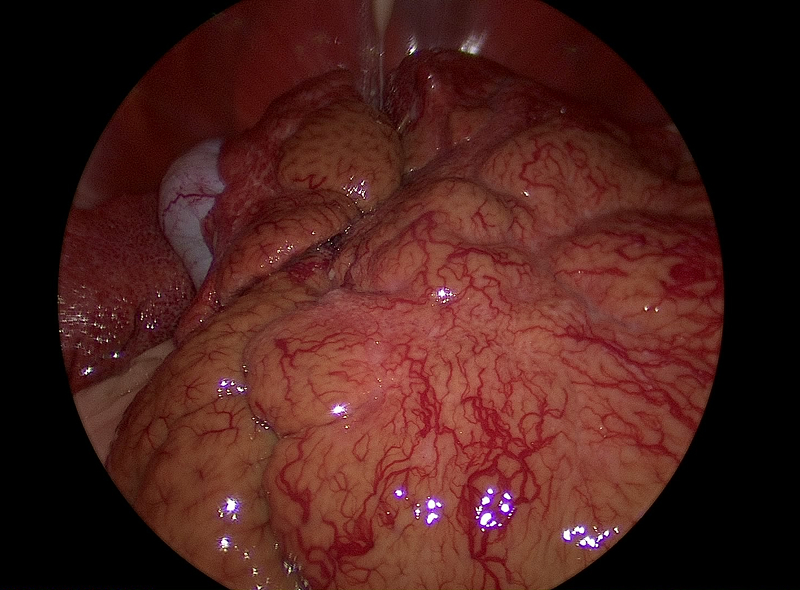

腹腔鏡下肝生検(肝硬変)

従来は上腹部を大きく切開し、肝生検を行っていました。

腹腔鏡手術では5mm、5mm、5mmの術創で手術が可能になります。

拡大された視野で臓器を観察することも可能です。胆汁培養採取も同時に実施できます。